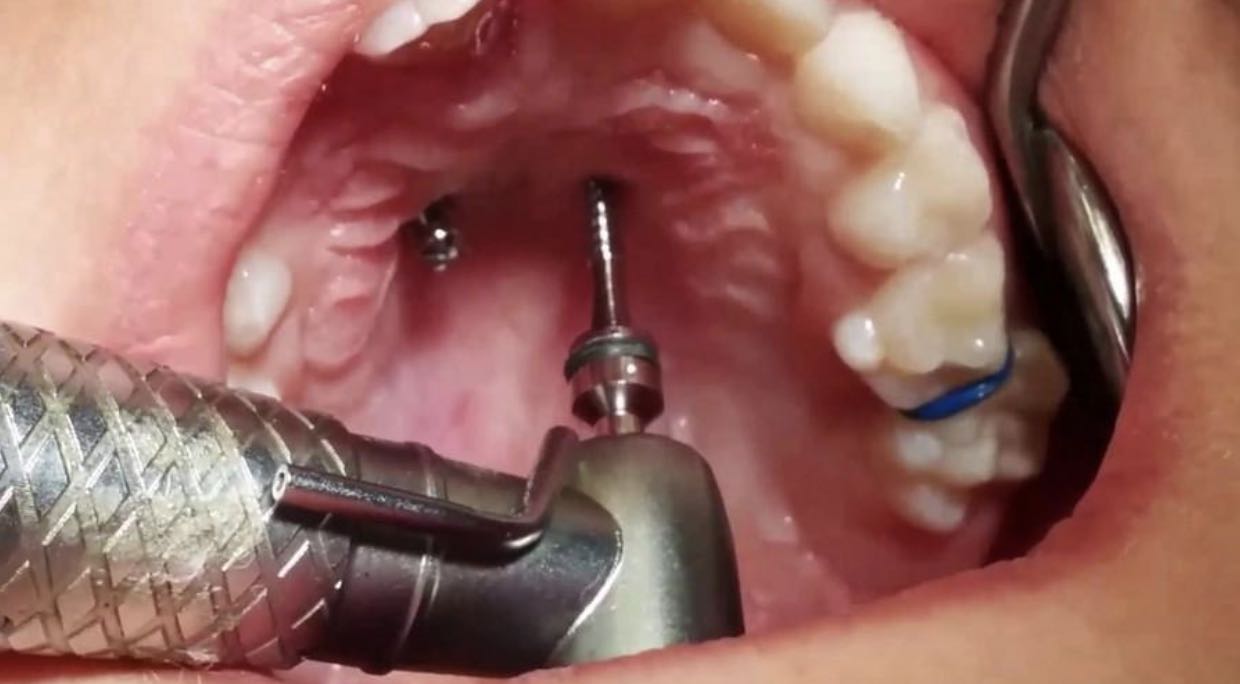

Установка микроимплантов

Лечение при помощи брекет-системы позволяет врачу использовать возможности не только дуги, но также микроимплантов. Их можно устанавливать и независимо от брекетов, например, на этапе подготовки для расширения верхней челюсти.